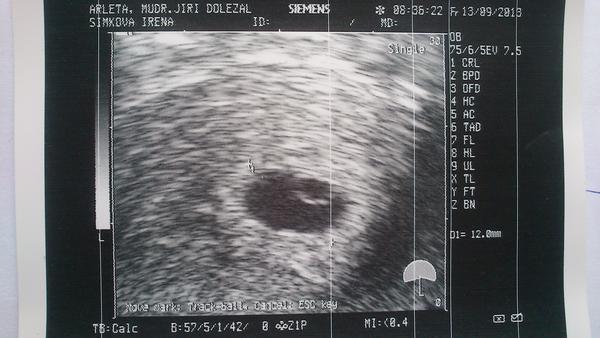

Ahoj kočenky. 🙂 Tak mimísek na utz je jeden a podle zprávy odpovídá 5+3,jinak jsme asi 5+4.Pan doktor říkal,že už vidí i srdíčko,ale já ho ještě pořádně neuvidím. 🙂 Je to na první fotečce ta šipečka.Jinak kontrola za 14 dní,to už dostanu i těhu průkazku a budou mi dělat odběry na prvotrimestrální screening.To zas bude nekonečných 14 dní......................... 😅 😅 😅 😅